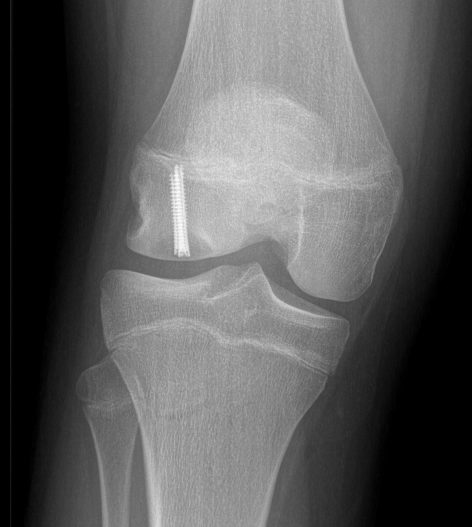

- typically 2 - 3 screws maximum (3.5 mm)

- 22 - 26 mm long, want to stop short of growth plate

Inferior screw Superior screw